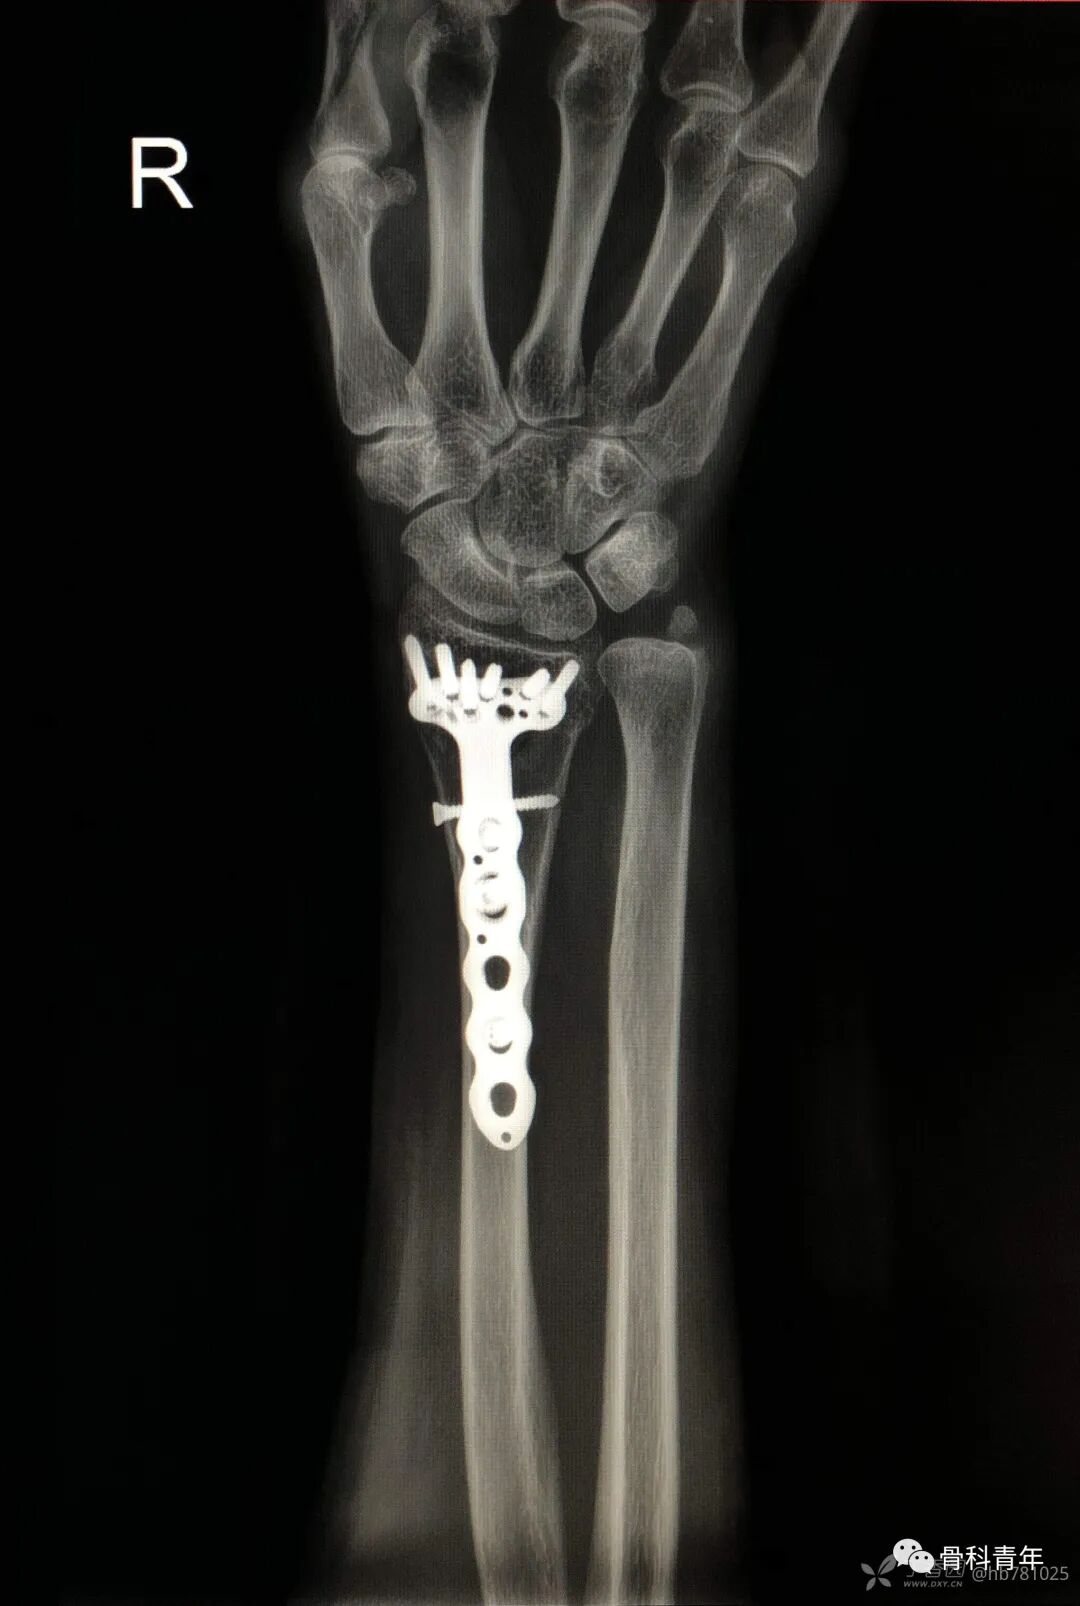

27.桡骨远端骨折